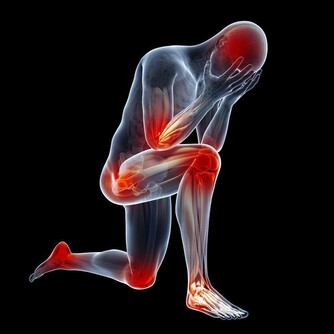

殊不知,此時醫院看骨科門診的人也逐漸增多,他們大多50歲以上,都是膝蓋的毛病,

一問才知道,很多人前不久才爬過山!

爬樓梯或爬山屬於負重運動,腰部以下的關節都要承受自己身體的重量,尤其膝蓋受力最多。

當身體爬階向上時,膝蓋負擔的重量會瞬間增為平常的4倍左右。

以一個體重60公斤的人為例:平路行走時,兩邊膝蓋各承重60公斤。

爬樓梯或爬山時,膝蓋負重瞬間變成240公斤,相當於左右膝蓋上各扛了一架鋼琴。

而且,速度越快,對膝蓋產生的壓力就越大。

而且,這種對膝蓋的磨損是不可修復的!磨損如果過度嚴重,只能夠置換關節!

在爬山和爬樓梯的時候,膝關節會承受超過本身體重3到4倍的壓力。

尤其是50歲以後,人的膝關節多少都會有些磨損的情況,此時,就要減少此類運動。